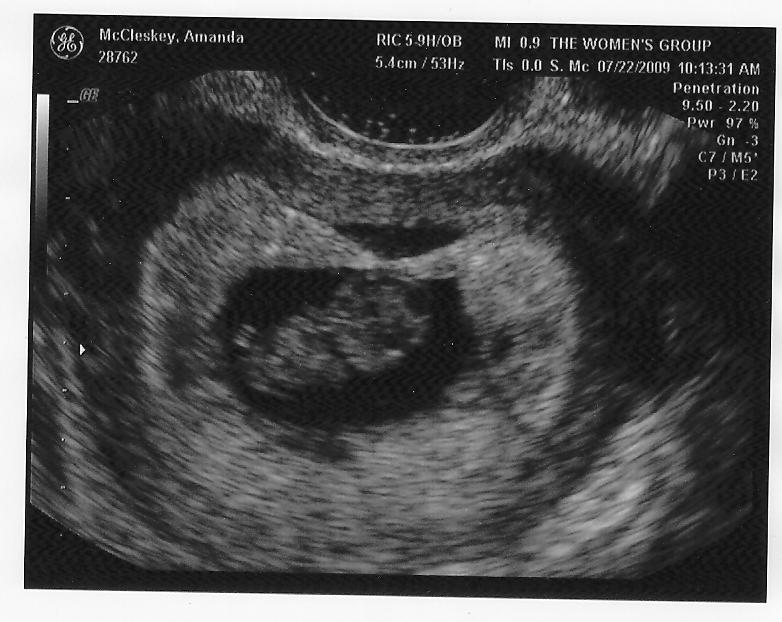

I will NEVER forget the feeling of sweet relief and overwhelming joy at seeing the smallest flicker of life on that black and white ultrasound machine. The immense, deep, never ceasing LOVE of Jesus flooded me so quickly in that moment & spilled over from Him to me and from me to the little spark within me.

And, then, my God, my God...5 weeks later and a heartbeat was heard. A heartbeat that stopped all of time for a moment. I didn't want them to take the wand away from my belly. I wanted the sound to go on forever. And the person growing within me, on the screen, small and perfectly at peace. Only knowing love.